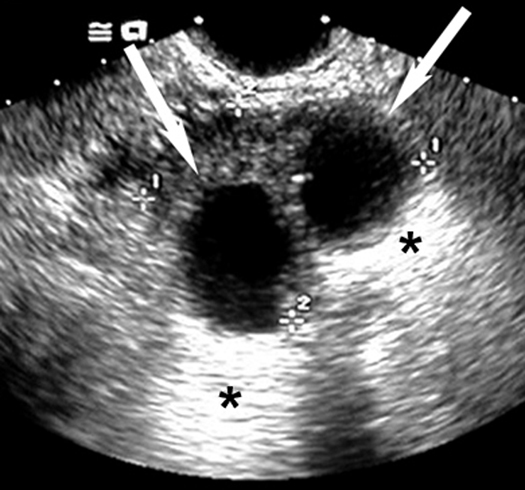

Simple Renal Cysts Most common in patients over 50 years of age.

These cysts are typically asymptomatic.

CT: Well defined mass with water [low] density usually in the renal cortex.

U.S Well marginated mass with no internal echoes and posterior enhancement indicating fluid.

Renal Cysts

Ultrasound can easily distinguish renal cysts from mass lesions.

Simple anechoic renal cysts

Arrows points to cyst.

* Points to good through transmission of echoes behind the cyst.